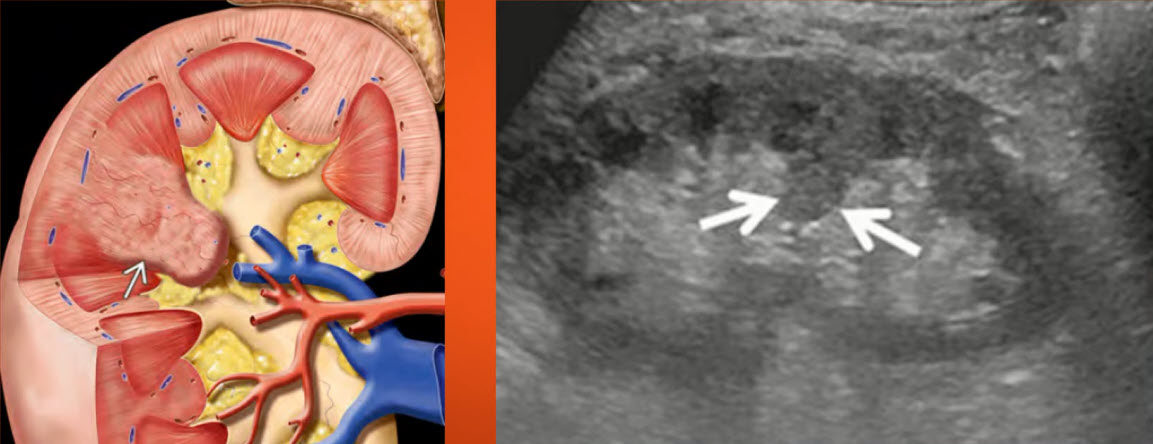

ЦДК сосудов почек: что это и как проводится

Раздел: Фотоэссе